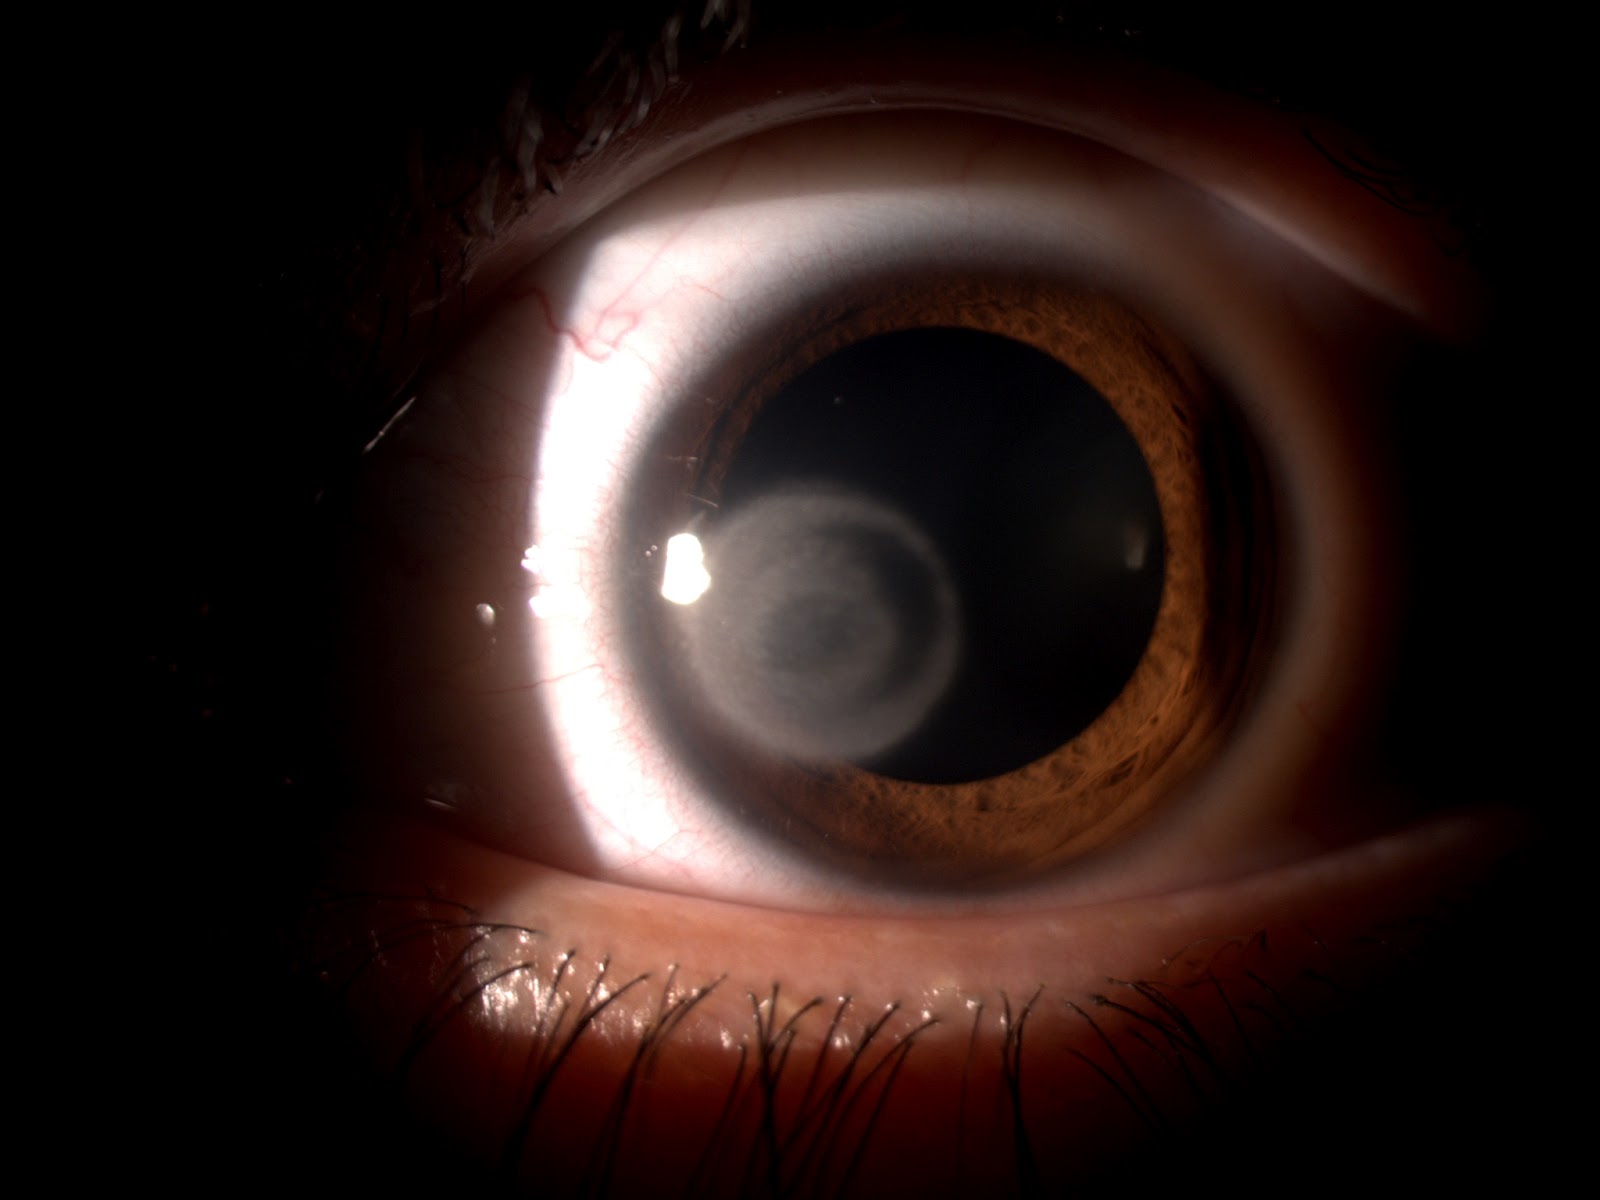

<li style="font-weight: 400;" aria-level="1"><b>Cataratas:</b><span style="font-weight: 400;"> se originan cuando el cristalino pierde su transparencia, opacándose e impidiendo el paso de la luz. Las proteínas del lente ocular comienzan a deteriorarse, lo que provoca una visión borrosa, la pérdida de nitidez y la disminución en la percepción de los colores. </span></li>

<p><span style="font-weight: 400;">El Instituto Mexicano de Oftalmología subraya la importancia de realizar controles médicos periódicos para detectar a tiempo posibles enfermedades oculares, entre las que destaca la catarata, considerada la principal causa de ceguera en la infancia. Esta condición ocular puede originar ambliopía, un trastorno que impide el desarrollo adecuado de la visión en los niños.</span></p>

<p><span style="font-weight: 400;">La catarata se refiere a la opacidad o pérdida progresiva de transparencia del cristalino, una estructura clave en el ojo humano que actúa como una lente natural. La causa de la catarata puede ser hereditaria o desarrollarse a raíz de infecciones, enfermedades metabólicas, traumatismos o anomalías en el desarrollo del ojo, entre otras razones.</span></p>

<p><span style="font-weight: 400;">En los países en desarrollo, la catarata es una de las principales causantes de la ceguera y de la pérdida de visión infantil, afectando a un alto número de niños en el mundo. Mientras que la ceguera es una patología frecuente en adultos debido al envejecimiento, en los niños es una condición anómala que debe ser tratada de manera urgente. </span></p>

<p><span style="font-weight: 400;">En resumen, la catarata infantil es una condición ocular que de no detectarse a tiempo puede llevar a la ceguera. Un diagnóstico temprano y un tratamiento adecuado, incluyendo cirugía y rehabilitación visual, son básicos para garantizar un buen pronóstico y un desarrollo visual saludable en los niños.</span></p>